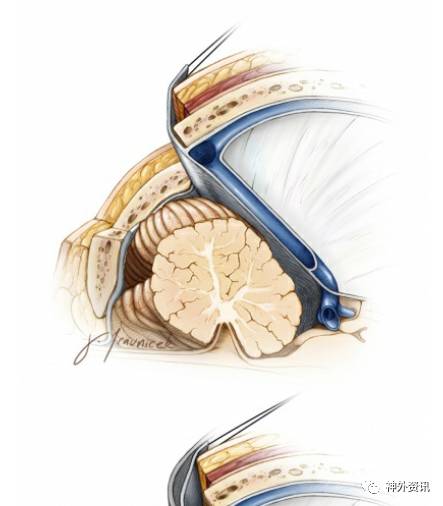

图10. 中线小脑上入路的钻孔位置和颅骨切开的程度如图。横窦表面的开颅时去掉铣刀踏板,只用铣刀头部(切开外板和板障),用B1 bit(金刚砂钻头)磨除颅骨。在开颅时颅骨撬开后横窦表面仅剩一层骨板时,可以应用磨钻磨开。打开硬膜(到横窦边缘)后轻轻向上翻转硬膜,缝合天幕并向上牵拉,以起到牵拉、抬起天幕(并显露)的作用 。枕骨大孔后缘的切开不是必需的。硬脑膜应该弧形切开。

图11. 传统颅骨和硬脑膜切开方法限制了医生的工作角度,同样限制了小脑上入路的显露空间(上图)。放置固定牵开器切开小脑幕,尽管可以抬起横窦,但是不能明显扩大手术视野,事实上,它可能还会影响到手术的工作角度(中间图片)。小脑幕上缝线并牵拉、抬起小脑幕,并可以抬起横窦,扩大手术视角(图)。

图12. 中线小脑蚓部桥静脉被电凝、切断。向Galen静脉引流的小脑中央前静脉,位于厚层蛛网膜覆盖的间脑静脉后部,并连接到山顶。手术显露需要牺牲此静脉,其它更多的位于前面的间脑静脉可以保留。注意牵拉、缝合的部位在小脑幕后部,这样的缝合、牵拉可以轻轻将横窦抬起并向上移位。